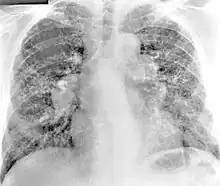

X-ray image of a 54-year-old man working in the aerospace manufacturing industry with berylliosis

Diagnosis of berylliosis is based on history of beryllium exposures, documented beryllium sensitivity, and granulomatous inflammation on lung biopsy. Given the invasive nature of a lung biopsy, diagnosis can also be based on clinical history consistent with berylliosis, abnormal chest x-ray or CT scan findings, and abnormalities in pulmonary function tests.[16]

The radiologic and pathologic features of berylliosis are very similar to sarcoidosis. Due to the strong clinical and histopathological resemblance of sarcoidosis and berylliosis, patients are sometimes misdiagnosed with sarcoidosis until the history of exposure to beryllium is elicited and beryllium hypersensitivity demonstrated with specific testing. Some studies suggest that up to 6% of all cases of sarcoidosis are actually berylliosis.[17] [18]

Chest radiography findings of berylliosis are non-specific. Early in the disease radiography findings are usually normal. In later stages interstitial fibrosis, pleural irregularities, hilar lymphadenopathy and ground-glass opacities have been reported.[20][21] Findings on CT are also not specific to berylliosis. Findings that are common in CT scans of people with berylliosis include parenchymal nodules in early stages. One study found that ground-glass opacities were more commonly seen on CT scan in berylliosis than in sarcoidosis. In later stages hilar lymphadenopathy, interstitial pulmonary fibrosis and pleural thickening.[21]